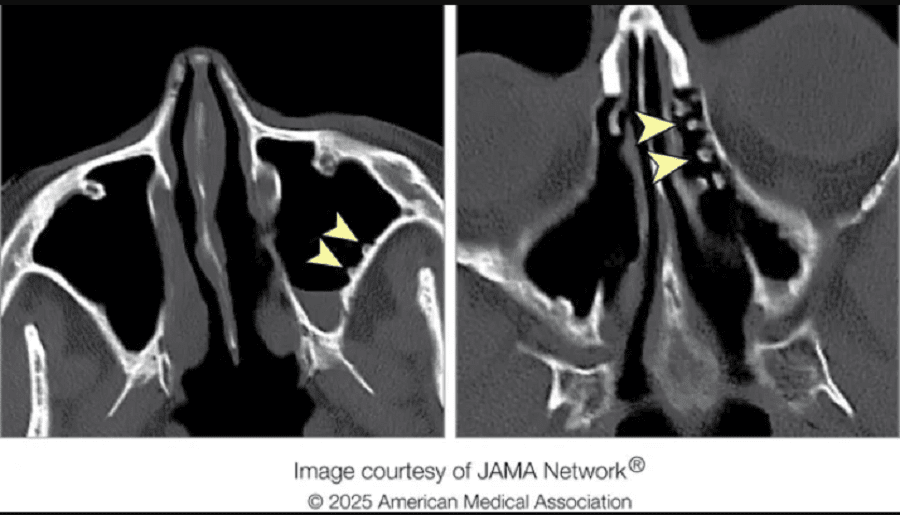

В США 35-летняя женщина обратилась к врачу с жалобами на заложенность носа и болезненные ощущения в области пазух. На первый взгляд — стандартный случай, но результаты эндоскопии удивили даже опытных специалистов: слизистая была покрыта множественными наростами, внешне напоминающими "булыжную мостовую".

По мнению врачей, воздействие холодной воды вызвало хроническое раздражение слизистой, что и спровоцировало образование атипичных наростов. Местная иммунная реакция, по-видимому, пошла по аномальному пути, активируя клеточную гиперплазию. В результате на стенках пазух выросли образования, схожие с булыжниками.